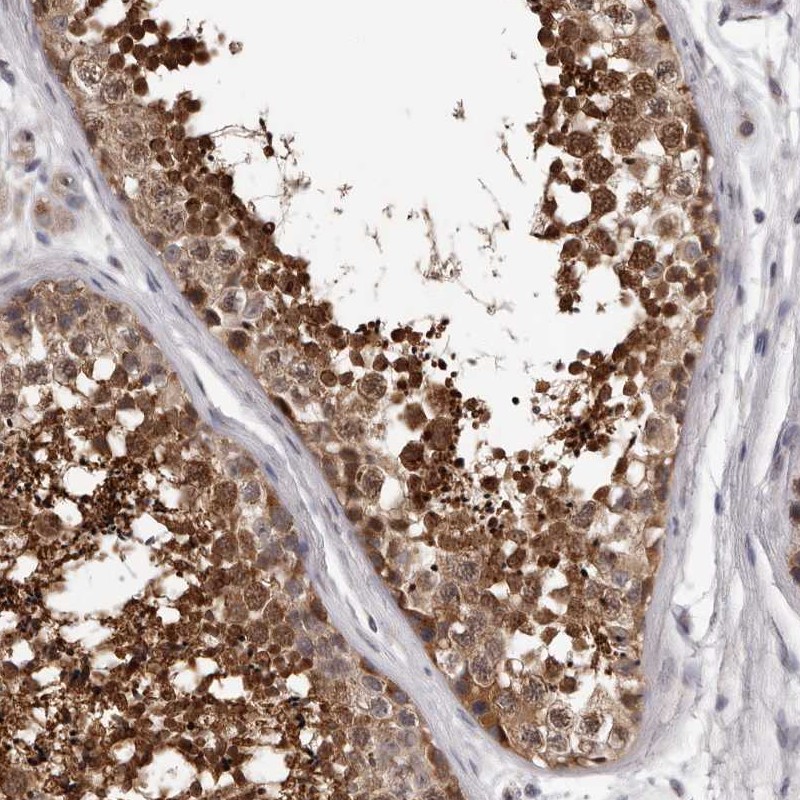

Immunohistochemical staining of human testis shows strong nuclear and cytoplasmic positivity in cells in seminiferous ducts.